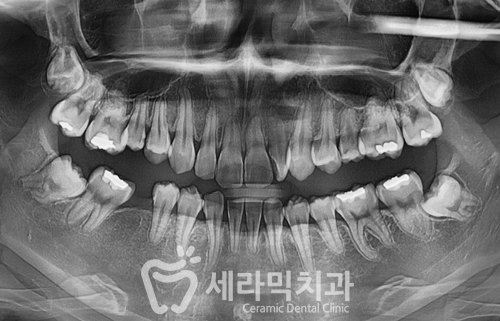

● 과개교합 치열불규칙 치아교정전후 사례자 프로필 ●

교정 시작 나이 : 21세

교정 시작 이유 : 과개교합, 치열불규칙

교정 치료 기간 : 17개월

치료방법 : 비발치 세라믹교정

● 치료계획 상세 ●

① 치아배열 좋지 않음

② Deep bite (과개교합)

③ #46 어금니 상실 상태

④ 아래 앞니 2개가 없음

⑤ 숨은 사랑니(매복 사랑니) 있음